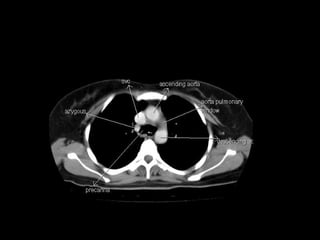

Radiographers use medical imaging equipment like X-rays and MRIs to produce images of patients' internal structures and organs. They are responsible for positioning patients, operating scanning machines, and ensuring quality images. Radiographers must have strong attention to detail, excellent communication skills, and the ability to work well under pressure to accurately capture anatomical features and diagnose any abnormalities.